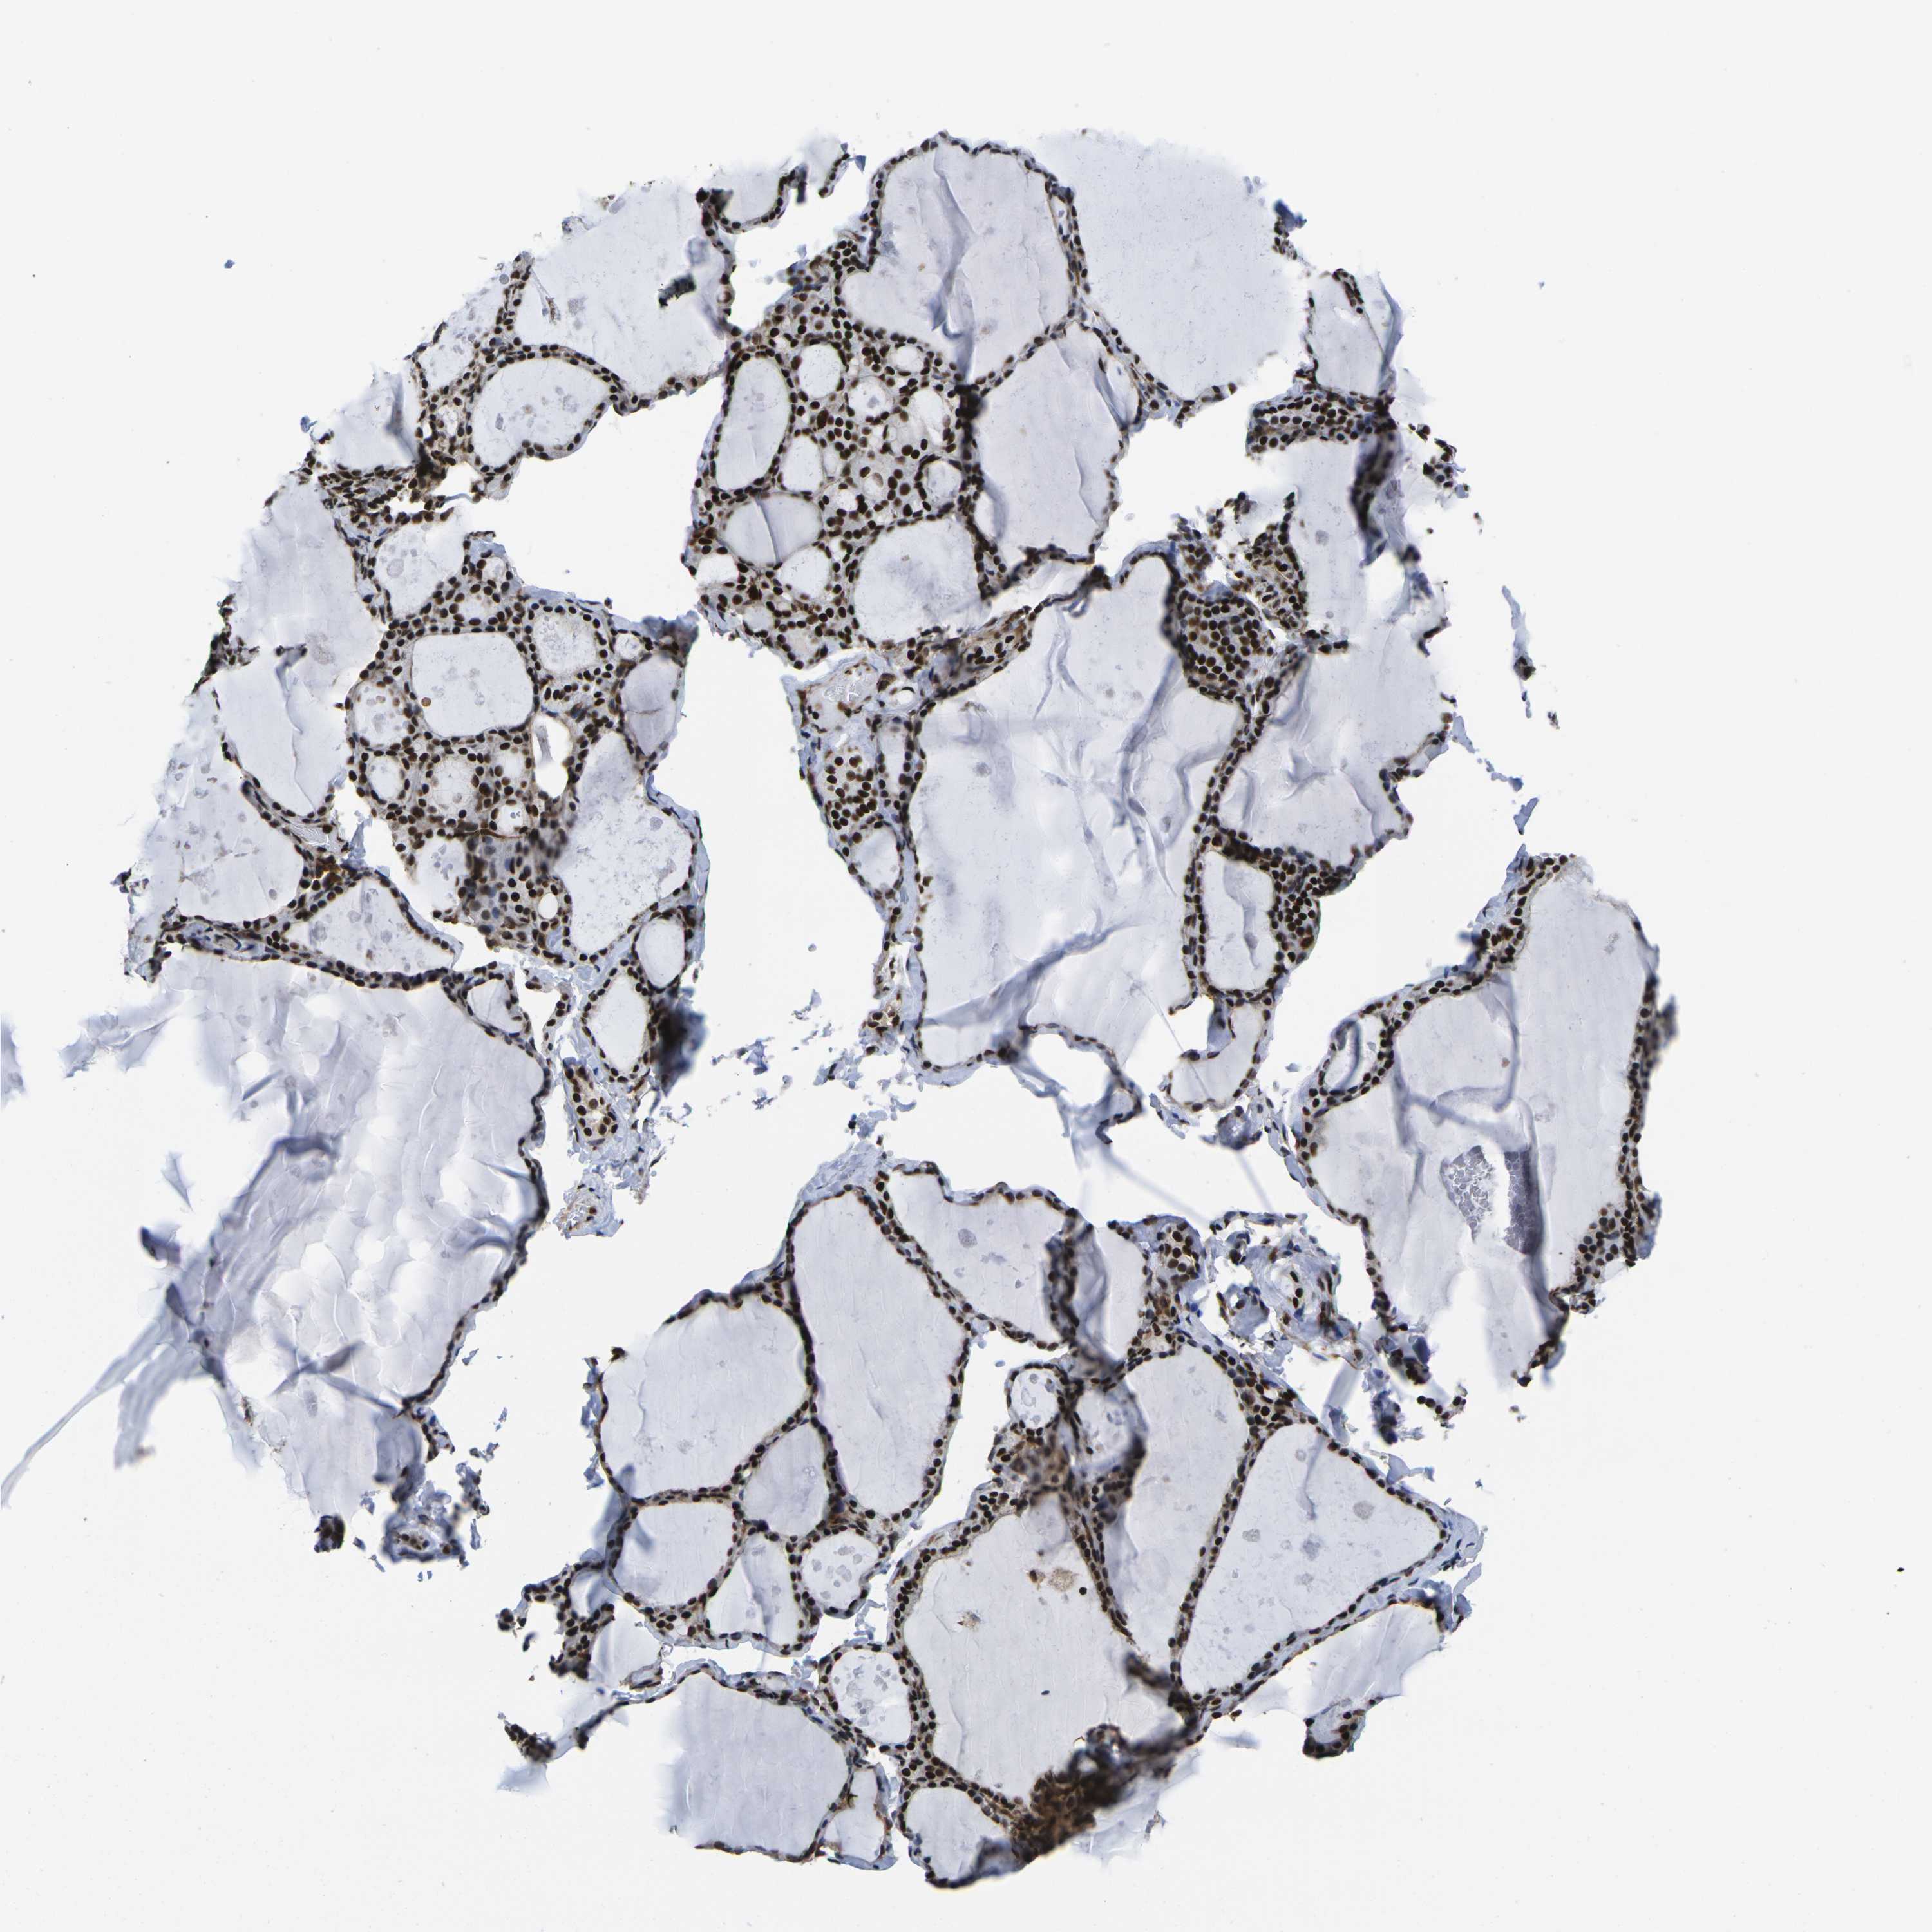

POLR2A